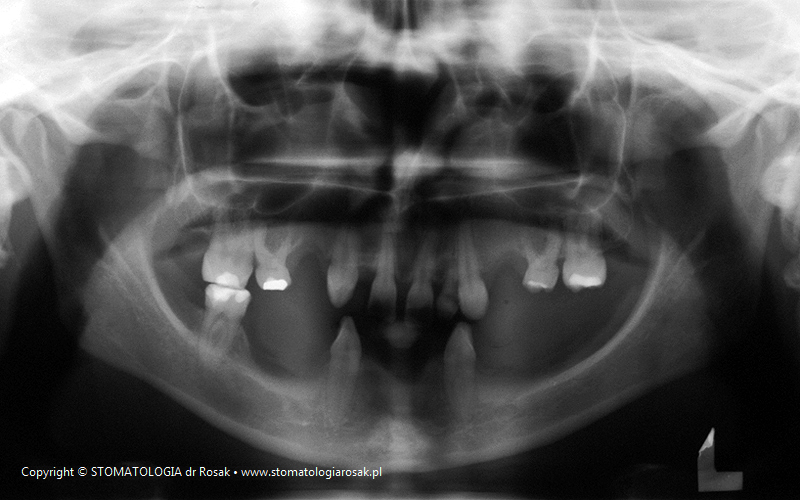

5. Pacjentka lat 18 z wrodzonym brakiem wielu zębów tzw. hipodoncją – rehabilitacja protetyczna z wykorzystaniem

stałych mostów porcelanowych na podbudowie metalowej.

| 5a. Stan przed leczeniem |

5b. RTG panoramiczne |